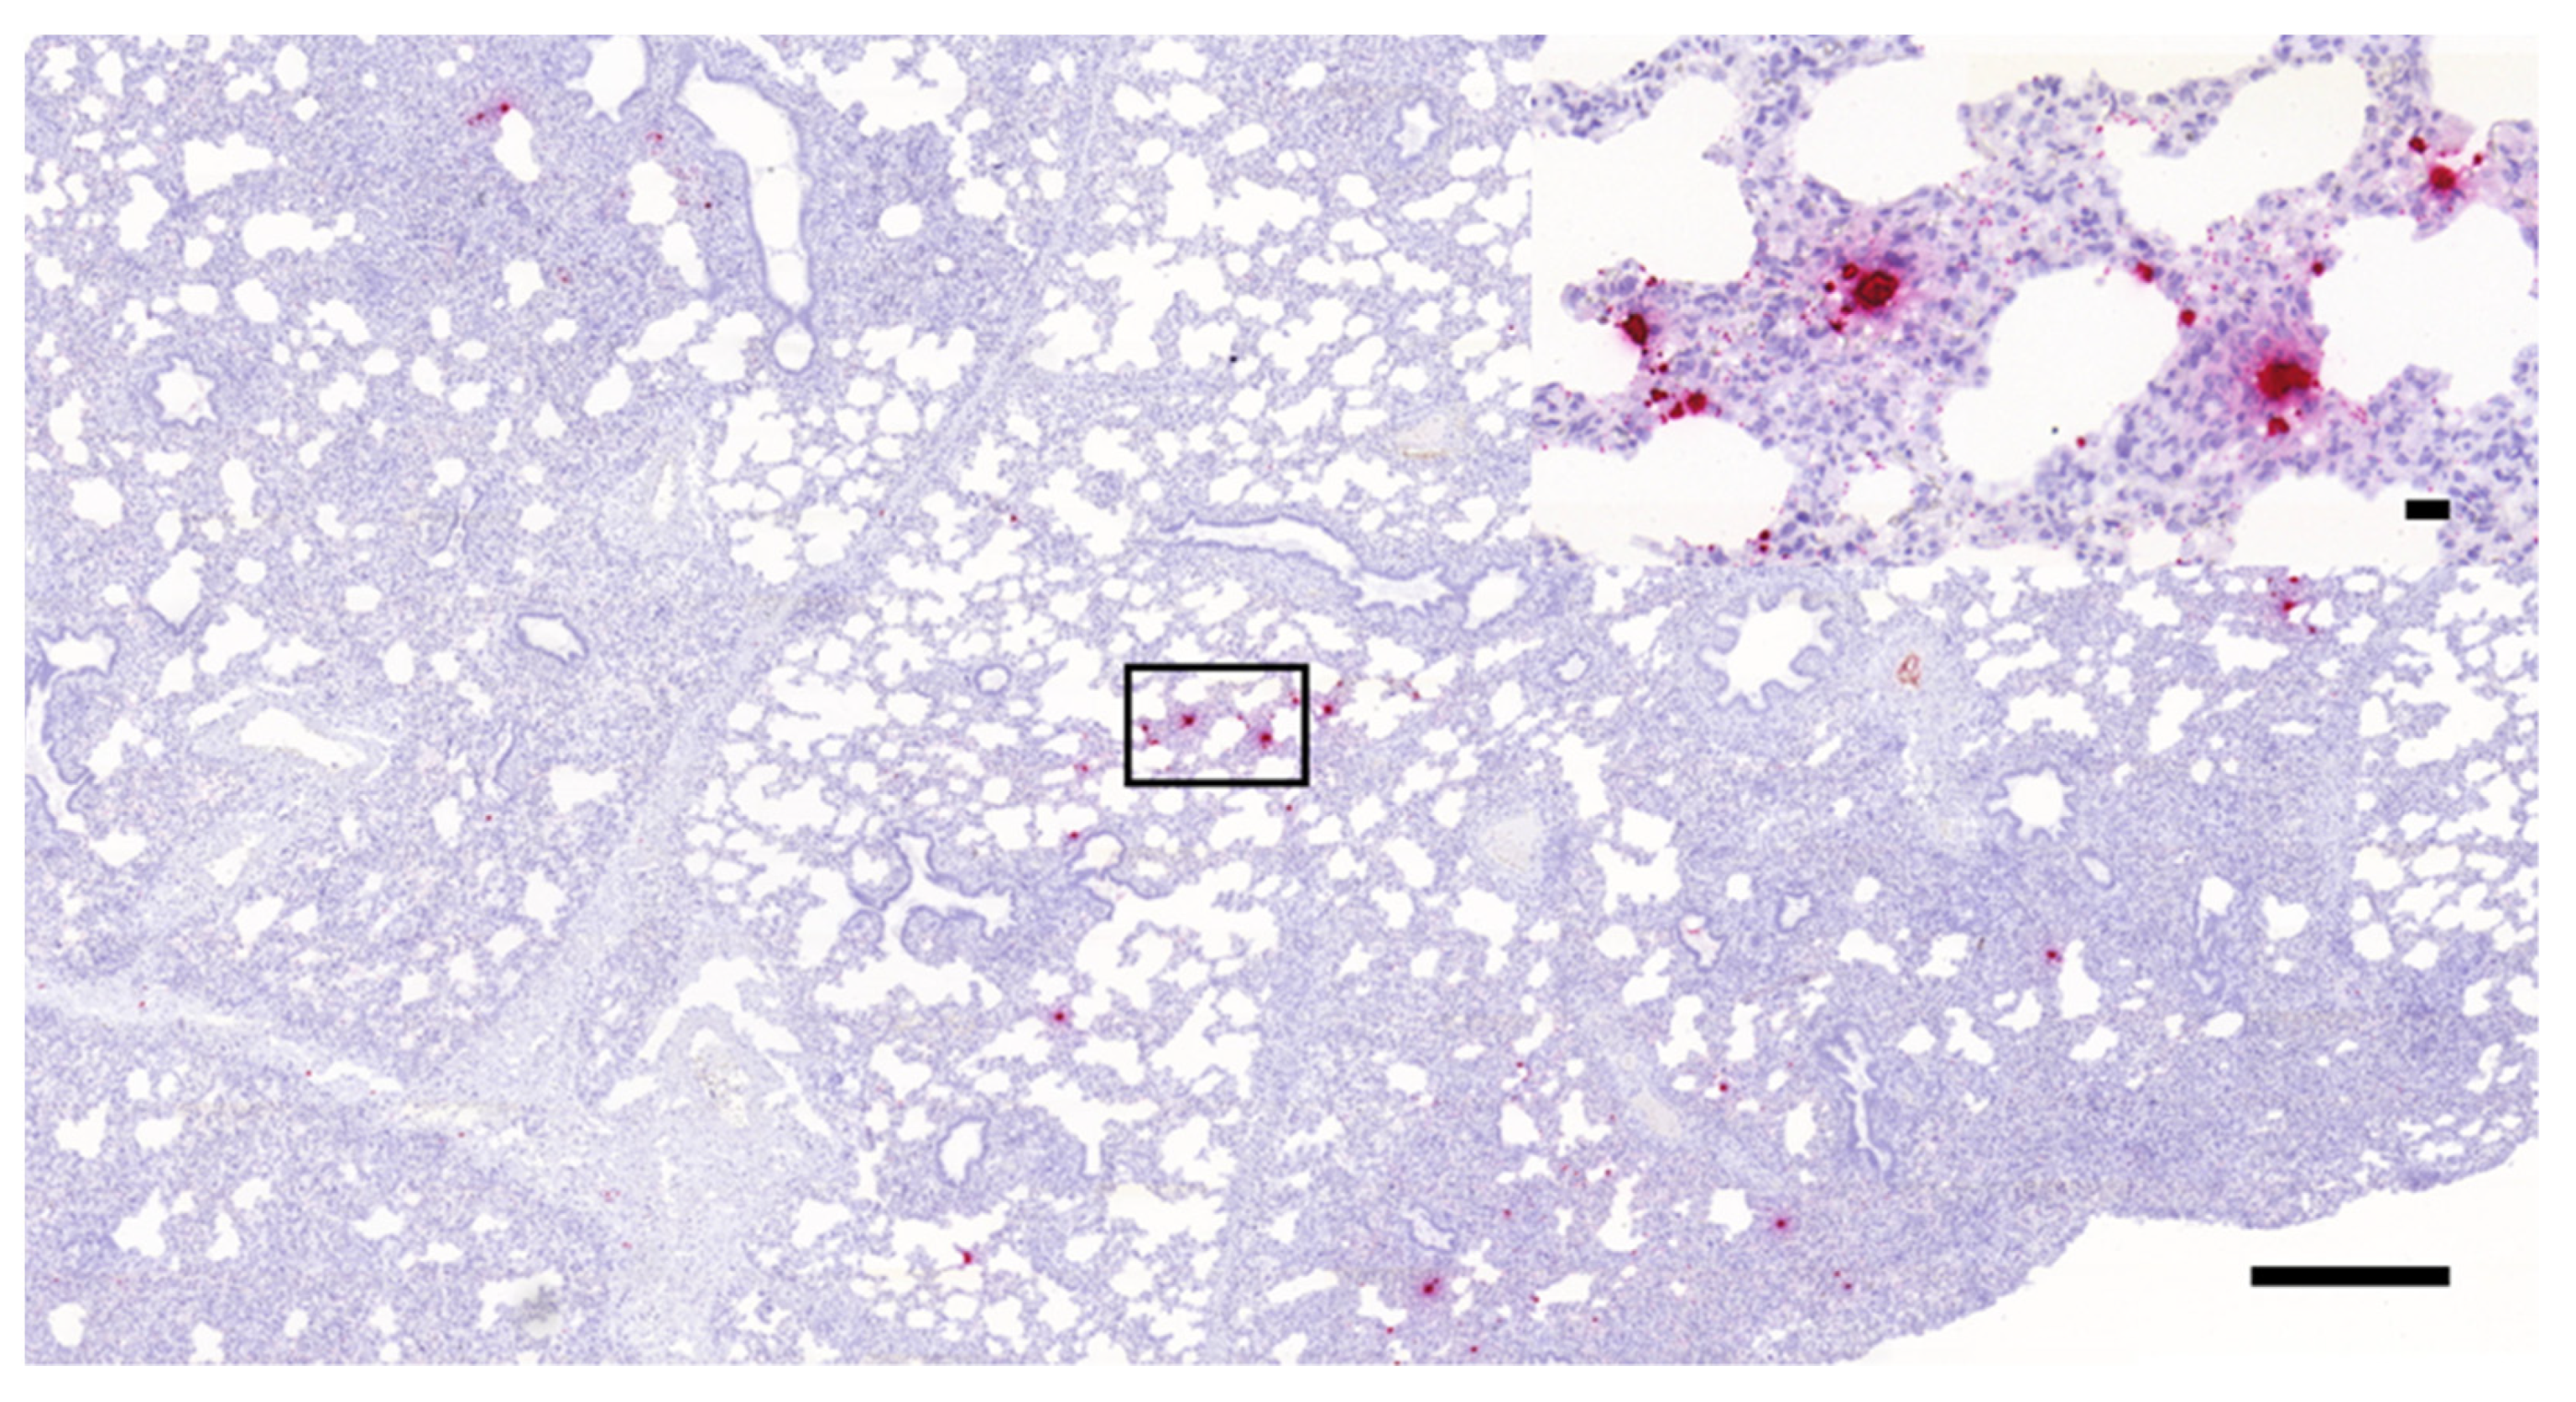

3.1. Histopathology and In Situ Hybridization